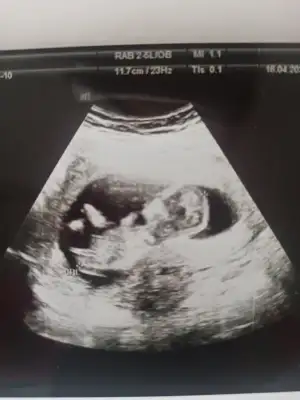

tahmın alabilir miyim karından ultrason 10+2🌸❤️